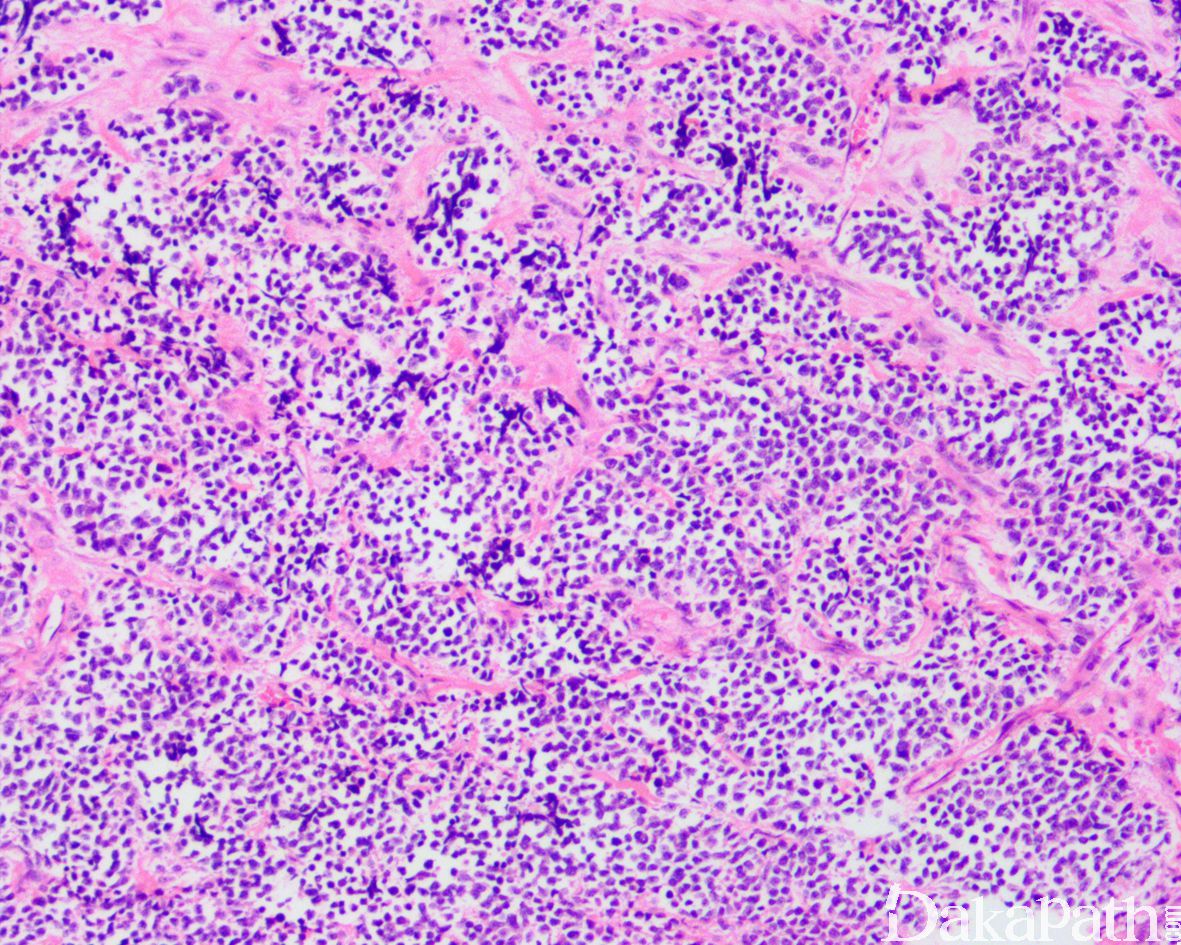

9. 实体型:

10. 由实性的瘤细胞巢组成,瘤细胞圆而较一致,具有纤细的空泡状染色质和小的核仁,部分病例瘤细胞胞质丰富而淡染或透明,类似肾透明细胞癌或软组织透明细胞肉瘤,称透明细胞变型;;

11. 仅偶见或无明显的假腺泡状结构。